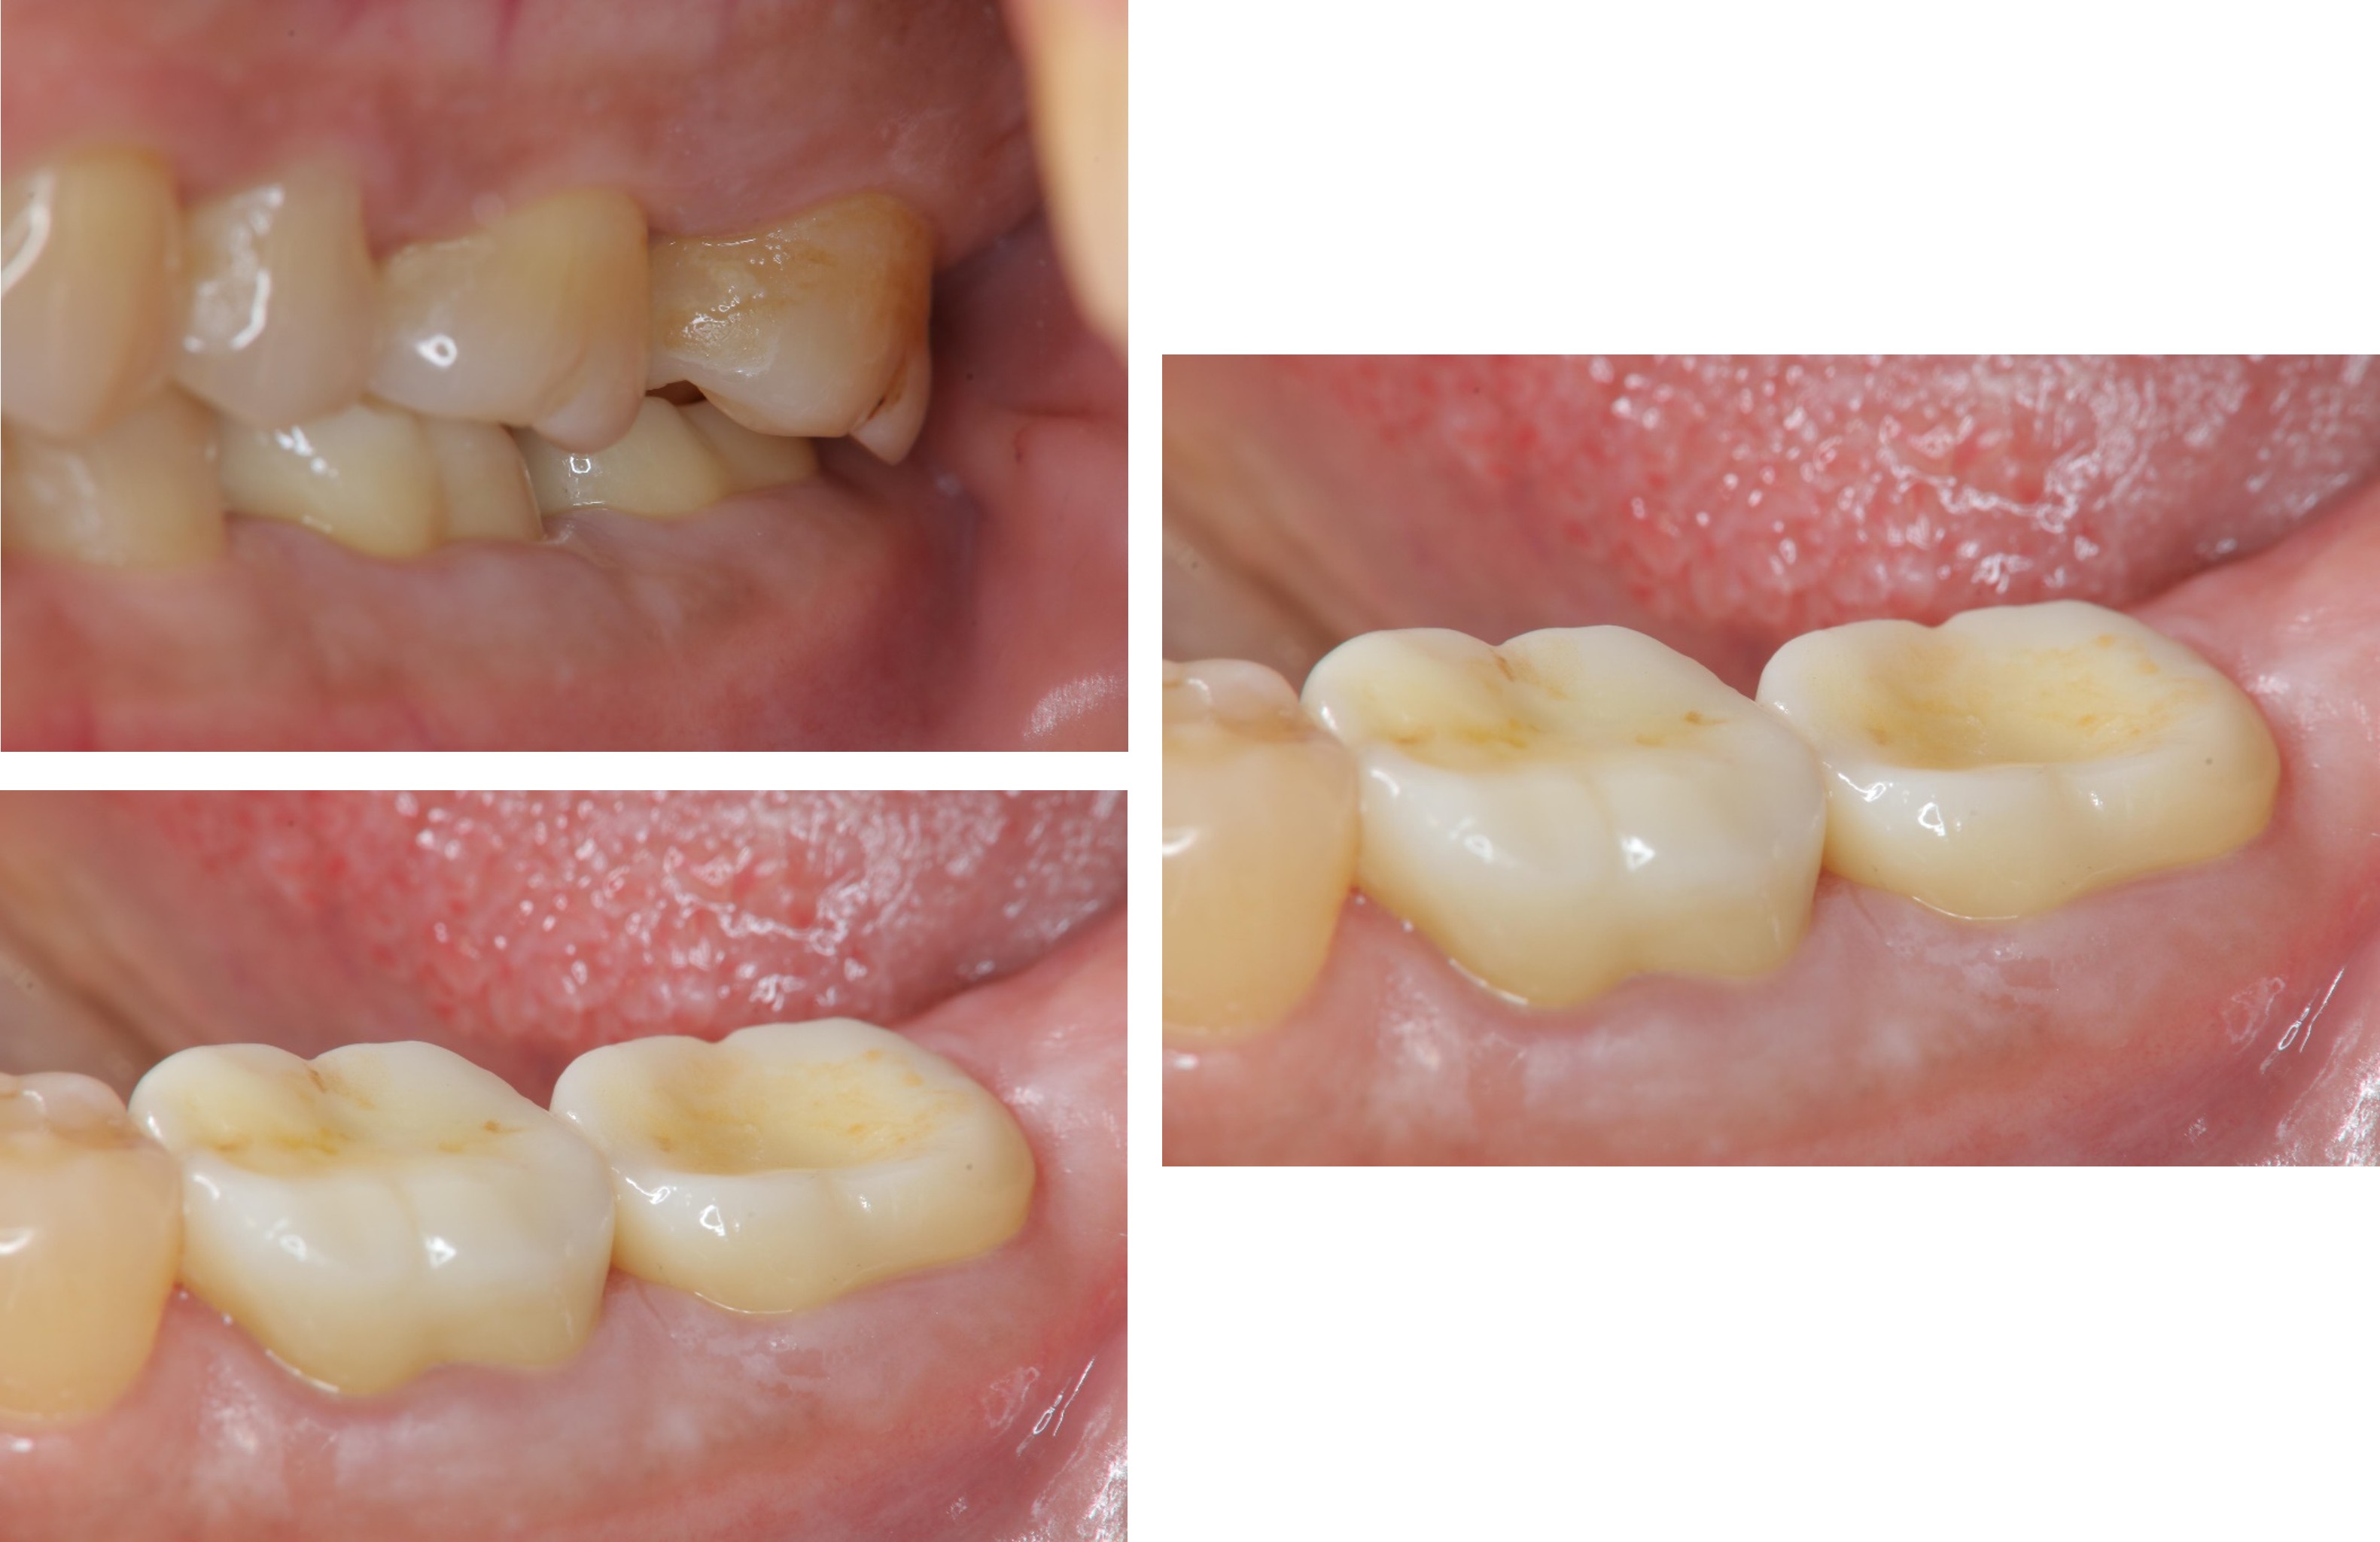

治療前,左下大臼齒區蛀牙

膺復前評估牙齦、牙齒狀態

術前、術後比較